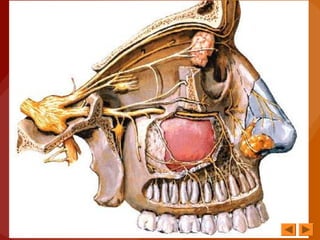

• Es un nervio sensitivo

• ORIGEN REAL

Células nerviosas situadas en la mucosa

olfatoria, que cubre la porción superior de

las paredes externa e interna de las fosas

nasales, desde la lámina cribosa del

etmoides hasta el borde inferior del cornete

superior

• ORIGEN APARENTE

Cara inferior del bulbo olfatorio

• Los filetes del nervio olfatorio discurren

por debajo de la mucosa olfatoria y llegan

convergiendo a la lámina cribosa del

etmoides

TRAYECTO